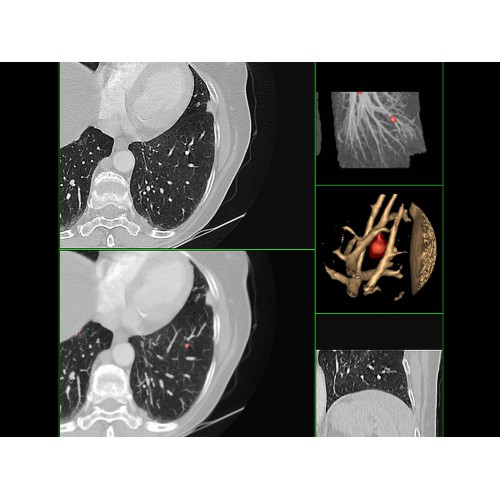

• Высокое качество изображения благодаря усовершенствованной системе реконструкции данных.

• Сниженная лучевая нагрузка на пациента без потери информативности снимков.

• Широкая область применения: от неврологии до кардиологии и онкологии.

Онкология

• Раннее выявление новообразований и контроль эффективности лечения.